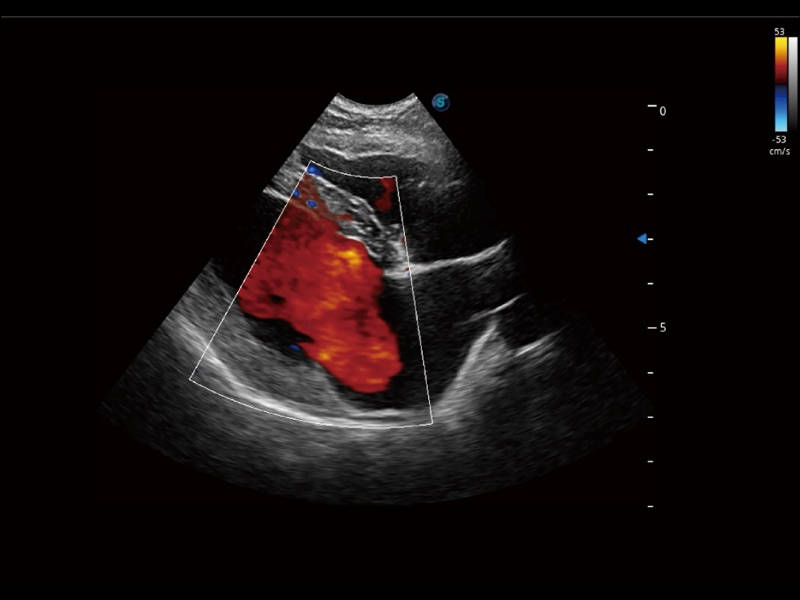

通过创新的 Matrix E自适应滤波器和超长时间域算法,极大提升超低速微细血流的检出能力,同时更精准地滤除软组织和噪声信号,为兽用医生提供以往无法通过常规血流获得的疾病诊断信息。

通过色彩血流和实时宽景相结合,可观察到完整的静脉或动脉的血流,方便医生检查。实时扫查过程中,如有任何操作失误也可以很容易地进行回扫擦除,而不会中断扫查。

通过360度任意调节3条M型取样线,在同一心动周期上观察心脏不同位置的运动曲线,得到准确的心功能测量数据,有效评估心肌运动及左心室功能。